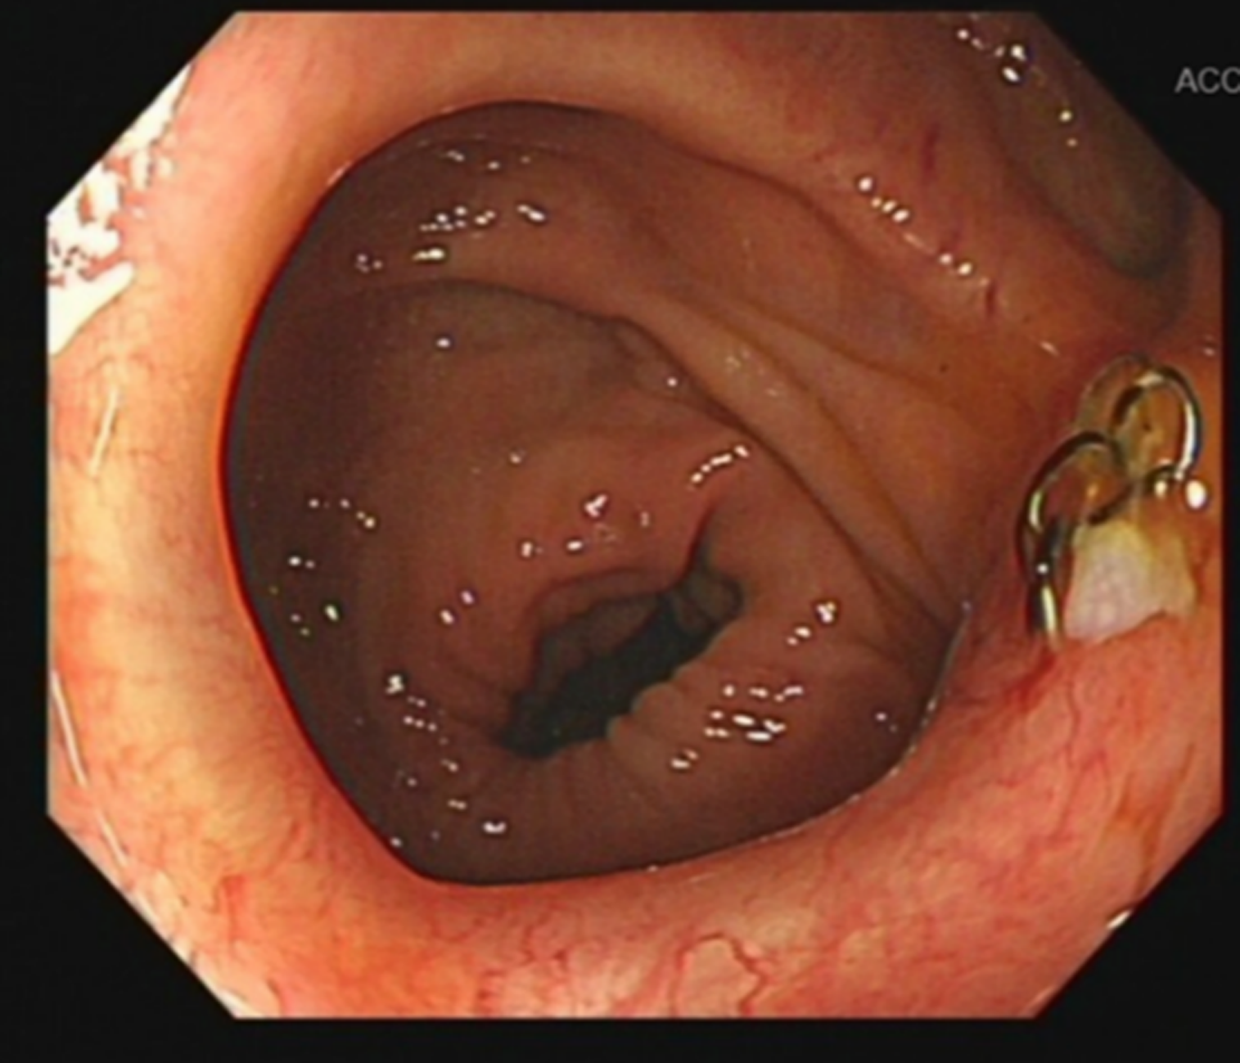

A 51-year-old man was diagnosed with rectal adenocarcinoma staged as cT3N2M0 over 3 years ago. Due to concerns regarding potential side effects on genitourinary and bowel function, he underwent three cycles of preoperative neoadjuvant chemotherapy using the FOLFOXIRI regimen, omitting radiotherapy. This regimen consists of a combination of fluorouracil, leucovorin, oxaliplatin, and irinotecan. Upon reassessment, his tumor showed shrinkage compared to previous evaluations. Consequently, the patient underwent robot-assisted laparoscopic low anterior resection with protective ileostomy on March 22, 2021. The left colonic artery was preserved during the operation to ensure better blood supply to the anastomosis. Postoperatively, the pathology indicated moderately differentiated adenocarcinoma, staged as pyT2N0M0. His recovery was uneventful, and he received six cycles of Capeox chemotherapy, which consisted of capecitabine and oxaliplatin. Prior to ileostomy reversal, the patient underwent a comprehensive examination including colonoscopy and CT scans, which showed no stricture at the rectal anastomosis and no evidence of recurrence or metastasis. The ileostomy was reversed at 153 days. Although the ileostomy reversal proceeded smoothly, he experienced increased stool frequency, approximately seven to eight times per day. Over the following 2 years, his bowel movements gradually decreased to three to six times per day, but he experienced prolonged and laborious defecation, with each stool passage taking more than 30 min. Colonoscopy and abdominal CT scan did not reveal anastomotic stenosis (with a diameter exceeding 1.5 cm), as evidenced by the smooth passage of a colonoscope at the anastomosis site (Figure 1). Upon digital rectal examination (DRE), the anastomotic ring could be felt at a distance of 3 to 4 cm from the anus, and there was no hindrance when passing the index finger through the anastomotic site. These symptoms caused significant distress to the patient, nearly rendering him unable to work. Despite visits to multiple medical centers, experts found no evidence of anastomotic stenosis and diagnosed him with LARS and functional bowel disease. He underwent treatment with laxatives, probiotics, biofeedback, and pelvic floor rehabilitation exercises, but his symptoms showed no improvement.

Figure 1

www.frontiersin.org

Figure 1 Colonoscopy showing anastomotic metal nails with no evidence of anastomotic stenosis.